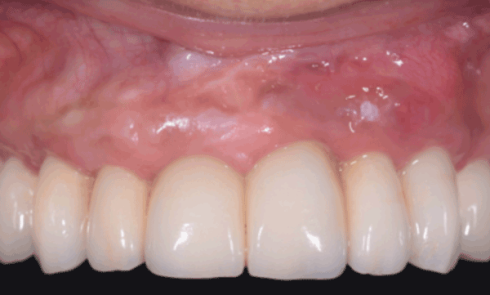

Article réservé à nos abonnés Hyperplasie gingivale ortho-induite traitée par gingivectomie

Cas clinique Une patiente de trente ans, traitée orthodontiquement pour une bi-proalvéolie (fig. 1) aggravée par la présence de diastèmes antérieurs...